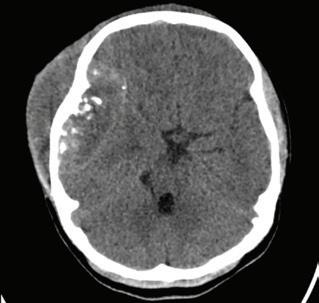

Posteriormente fue manejada con AINES, pero con aumento en tamaño de la lesión y dolor incre mentando con el tiempo hasta que decidió consul tar nuevamente. En esta ocasión se realiza TAC de cráneo en septiembre de 2022, con reporte de lesión extra axial heterogénea que compromete la región parietal temporal y frontal derecha de 82*28*62 mm, y patrón permeativo y alteración de los tejidos blandos adyacentes con realce en forma heterogé nea en medio de contraste. Debido a este reporte le indican a su madre que requiere otro nivel de aten ción, por la complejidad de la lesión y la remiten a nuestra institución.

Se hospitaliza del 9 de septiembre de 2022, reali zando TAC de cráneo (Imagen 1) al día 21 del mis mo mes, con diagnóstico de tumor agresivo a nivel frontotemporal derecho realizando resección macro intraoperatoria con bordes sanos. Dura no infiltra da el día 13 de ese mes sin complicaciones. Realizan TAC control (Imagen 2), posteriormente sin residuo tumoral evidente con hematoma extradural, en ese momento se decide manejo médico.

Imagen 1. Tac de cráneo: Se identifica una lesión extraaxial frontotem poral derecha con áreas de mayor densidad y calcificaciones en el interior con erosión, y lisis del diploe con extensión a los tejidos blandos adya centes; alcanzando unas medidas máximas de 82 x 53 mm. Tiene efecto de masa comprimiendo el parénquima adyacente y desplazando la línea media derecha izquierda aproximadamente 10 mm.